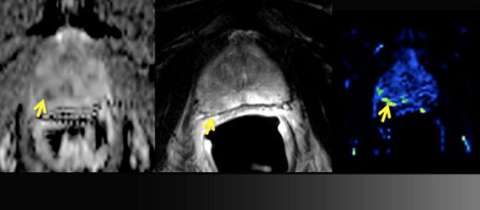

LEFT: Apparent diffusion coefficient (ADC) map: moderately restricted diffusion

CENTER: T2 Weighted imaging: ill-defined low signal (yellow arrow) does not abut the prostate capsule

RIGHT: Perfusion map: focally increased perfusion